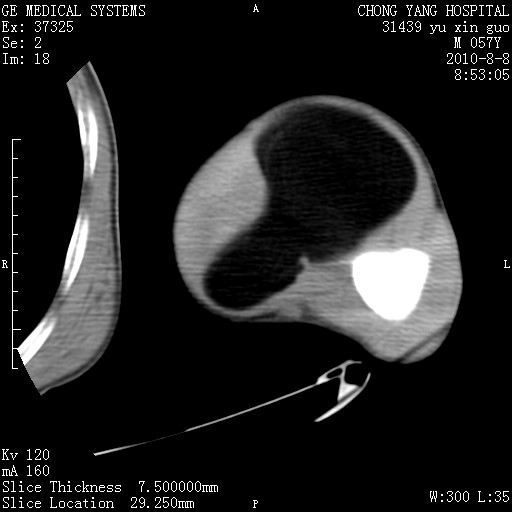

标题: CT28267:M57Y 上臂包块8年余。 [打印本页]

标题: CT28267:M57Y 上臂包块8年余。

典型脂肪瘤改变

上臂软组织内脂肪瘤。

包膜光滑、完整的脂肪密度肿块,支持脂肪瘤。

脂肪瘤。有ct值?